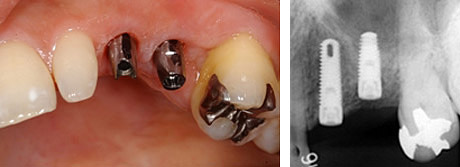

上顎前歯部のインプラント

この症例は、折れてしまった前歯をインプラントで治療した例です。

治療前:右上前歯の破折で患者さんは来院されました。

残念ながら、患歯は治療することができず抜歯になりました。以前は、このような状態をブリッジで治していましたが、きれいなとなりの歯を削ることなくこの状態を治す方法として、インプラントは優れています。

治療後:天然歯と見分けがつかないぐらいに治っています。

乳歯を2本抜歯し、インプラントを植立しました。右は、植立後4ヵ月のエックス線写真、左は、アバットメント装着時の口腔内写真です。